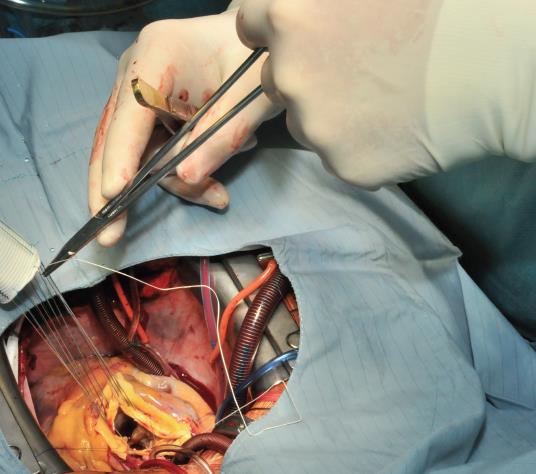

The procedure starts with the proximal suture of the composite graft prosthesis to the aortic annulus using separated mattress suture of 2.0 Ethibond backed with small Teflon pledgets. The first suture is placed at the level of the commissure between the left and right coronary sinuses and the following are stitched in a clockwise fashion (Image 1). The sutures are placed through the annulus with the pledgets left either on the aortic side thus everting the annulus, but in small annular diameters. The author prefers to stich these sutures from the ventricular side to the aorta, therefore the pledgets lie under the aortic annulus. Then the sutures are placed through the sewing ring of the composite graft prosthesis (Image 2) which is later on parachuted down to the aortic annulus (Image 3). The sutures are then tightened and the valve is placed into the outflow tract of the left ventricle (this provides excellent hemostasis).

Image 2: The sutures are passed through the sewing cuff of the valve. In this case, the Teflon pledgets were placed below the aortic annulus. Alternatively, the stitches can be performed from the aortic side (outside-in) leaving the Teflon pledgets outside of the blood flow. This is especially favorable in case when the size of the aortic annulus has to be reduced.

Image 3: The composite graft is then parachuted into the aortic annulus (mechanical valve) or placed in a supra-annular position when a bioprosthetic valve has been used. The sutures are tightened and cut. At this time, the core temperature has usually be brought to 28 or 30°C to proceed with the distal anastomosis at the level of the proximal (open) aortic arch.